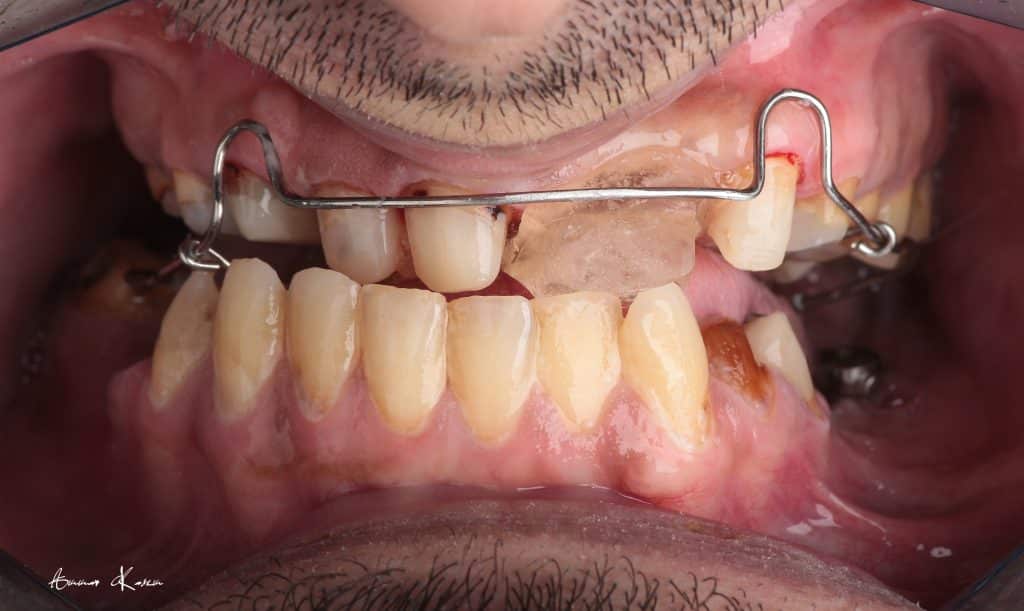

The patient was normally class I occlusion type ( according to old photos and cephalometric analysis) till he received this defective restorations 10 years ago

With time, the mandible shifted till become habitual class III

3- Deprogramming to release stresses and to adjust the new occlusion

4- Facebow records and mounting on semi adjustable articulator

5- 1st mock up ( edge to edge ) for 2 months